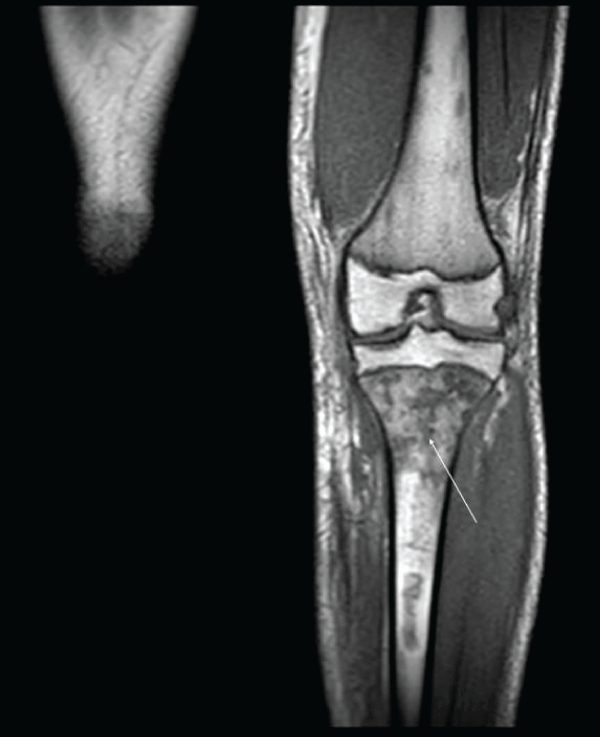

Figure 1:

MRI of the knee joint. In the proximal metaphysis and diaphysis of the left tibia, there is a marked alteration in signal intensity, which appears hyperintense at T2 and hypointense at T1, with multiple well-defined focal lesions of serpiginous and irregular morphology suggestive of multiple bone infarctions in the context of osteomyelitis.